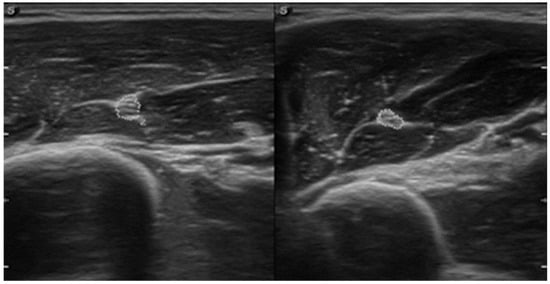

| July | Symptoms: brachialis muscle atrophy (Figure 1 and Figure 2) (pain 4/10 NPRS). Assessment: medical history, physical examination, ultrasound (orthopaedic surgeon). Diagnosis: unspecified soft tissue diseases associated with their use overload and overexertion (M70.9 ICD). Treatment: pharmacological treatment, avoid full weight-bearing. Effects: no positive therapeutic effect. |

| October | Symptoms: episodic of more severe pain, paraesthesia, tingling, numbness and burning sensations of right upper limb, (pain 3/10 NPRS). Assessment: medical history, physical examination (another orthopaedic surgeon), shoulder (Figure 3) and elbow MRI order (the same orthopaedic surgeon), cervical spine MRI order, electromyography, nerve conduction study (Table 2 and Table 3) (another orthopaedic surgeon), medical history, physical examination, ultrasound (another physiotherapist). Diagnosis: mononeuropathy of the upper limb, unspecified (G56.9 ICD) (orthopaedic surgeon), PTS suggestion (physiotherapist) Treatment: orthopedy surgeon: physiotherapy (massage, muscle relaxation, electrostimulation, exercises); physiotherapist recommendation: neurodynamic techniques. Effects: no positive effect. |

| CSA | affected | 0.09 cm2 | 0.06 cm2 |

| non-affected | 0.06 cm2 | 0.06 cm2 | |